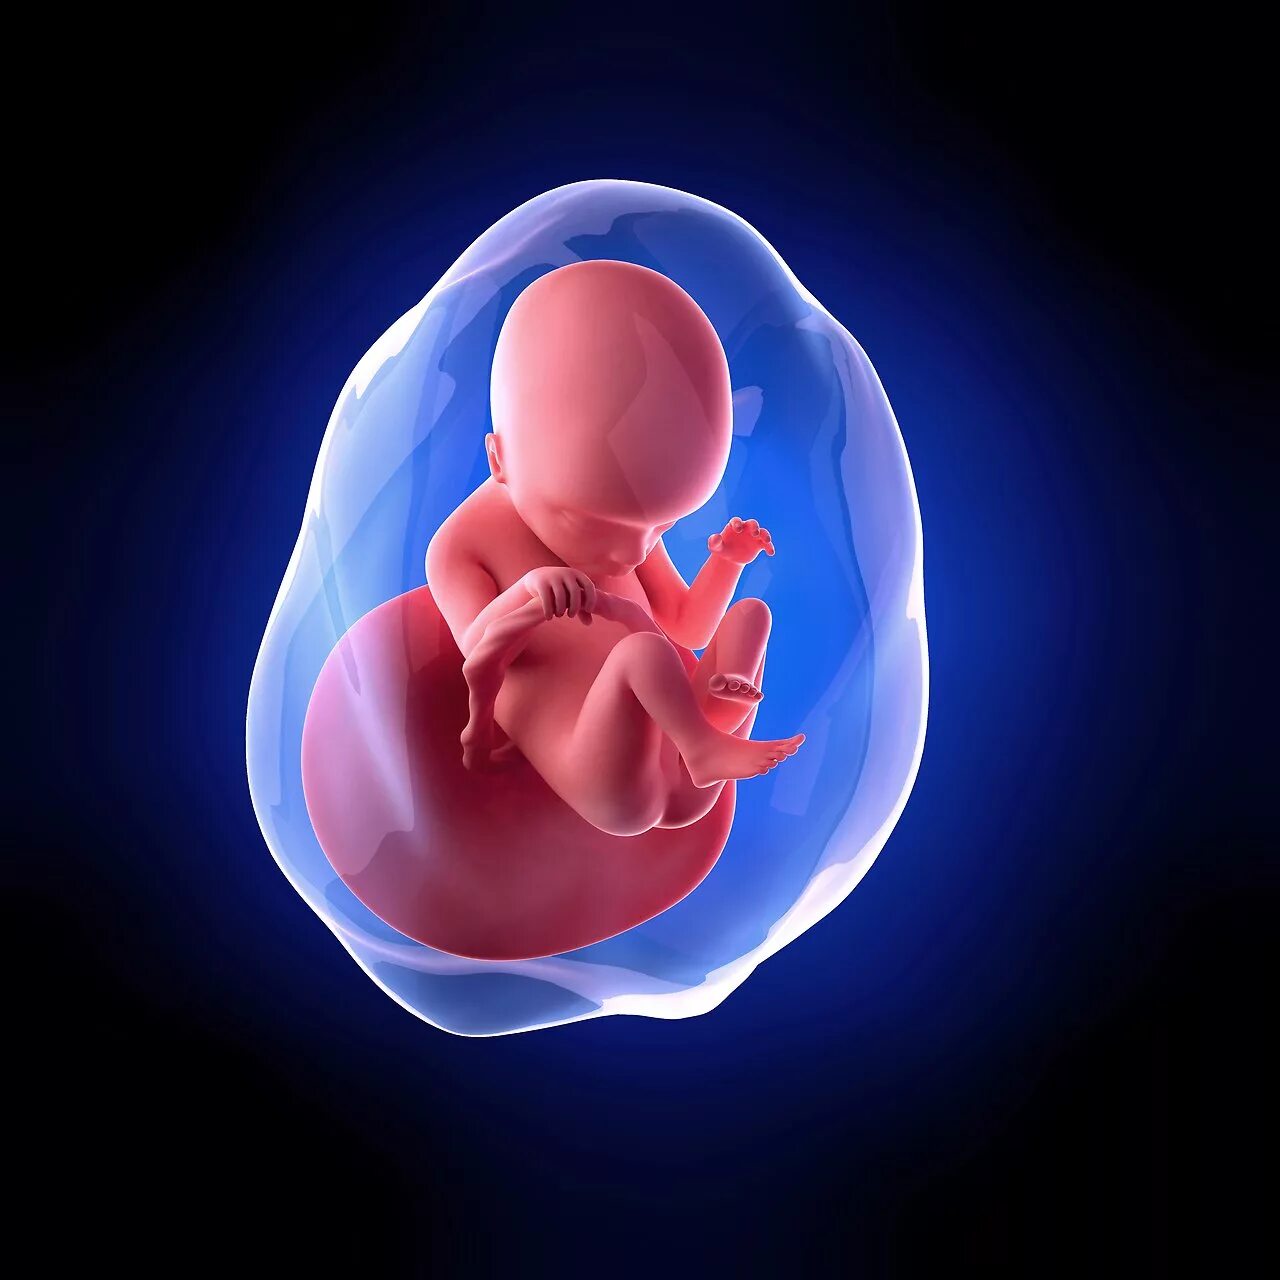

Как выглядит ребенок в 18 недель